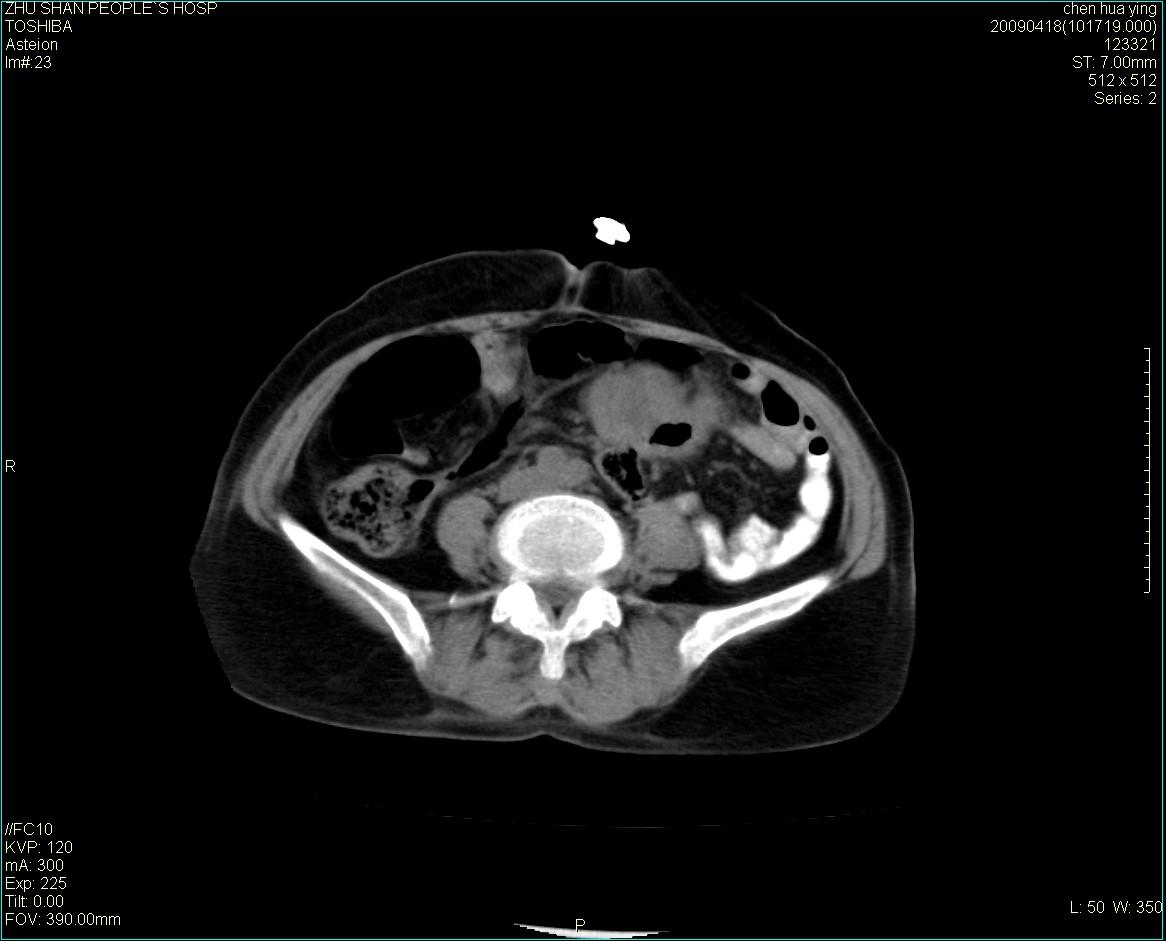

女性病人 65岁 腹部包块半年余结肠造影未见异常.

病灶略呈圆形有分叶状,上部层面呈实性,右侧见圆形低密度区,灶内见团块状钙化,病灶下方与肠管分境不清,考虑间质瘤可能性大,建议肠道准备后增强